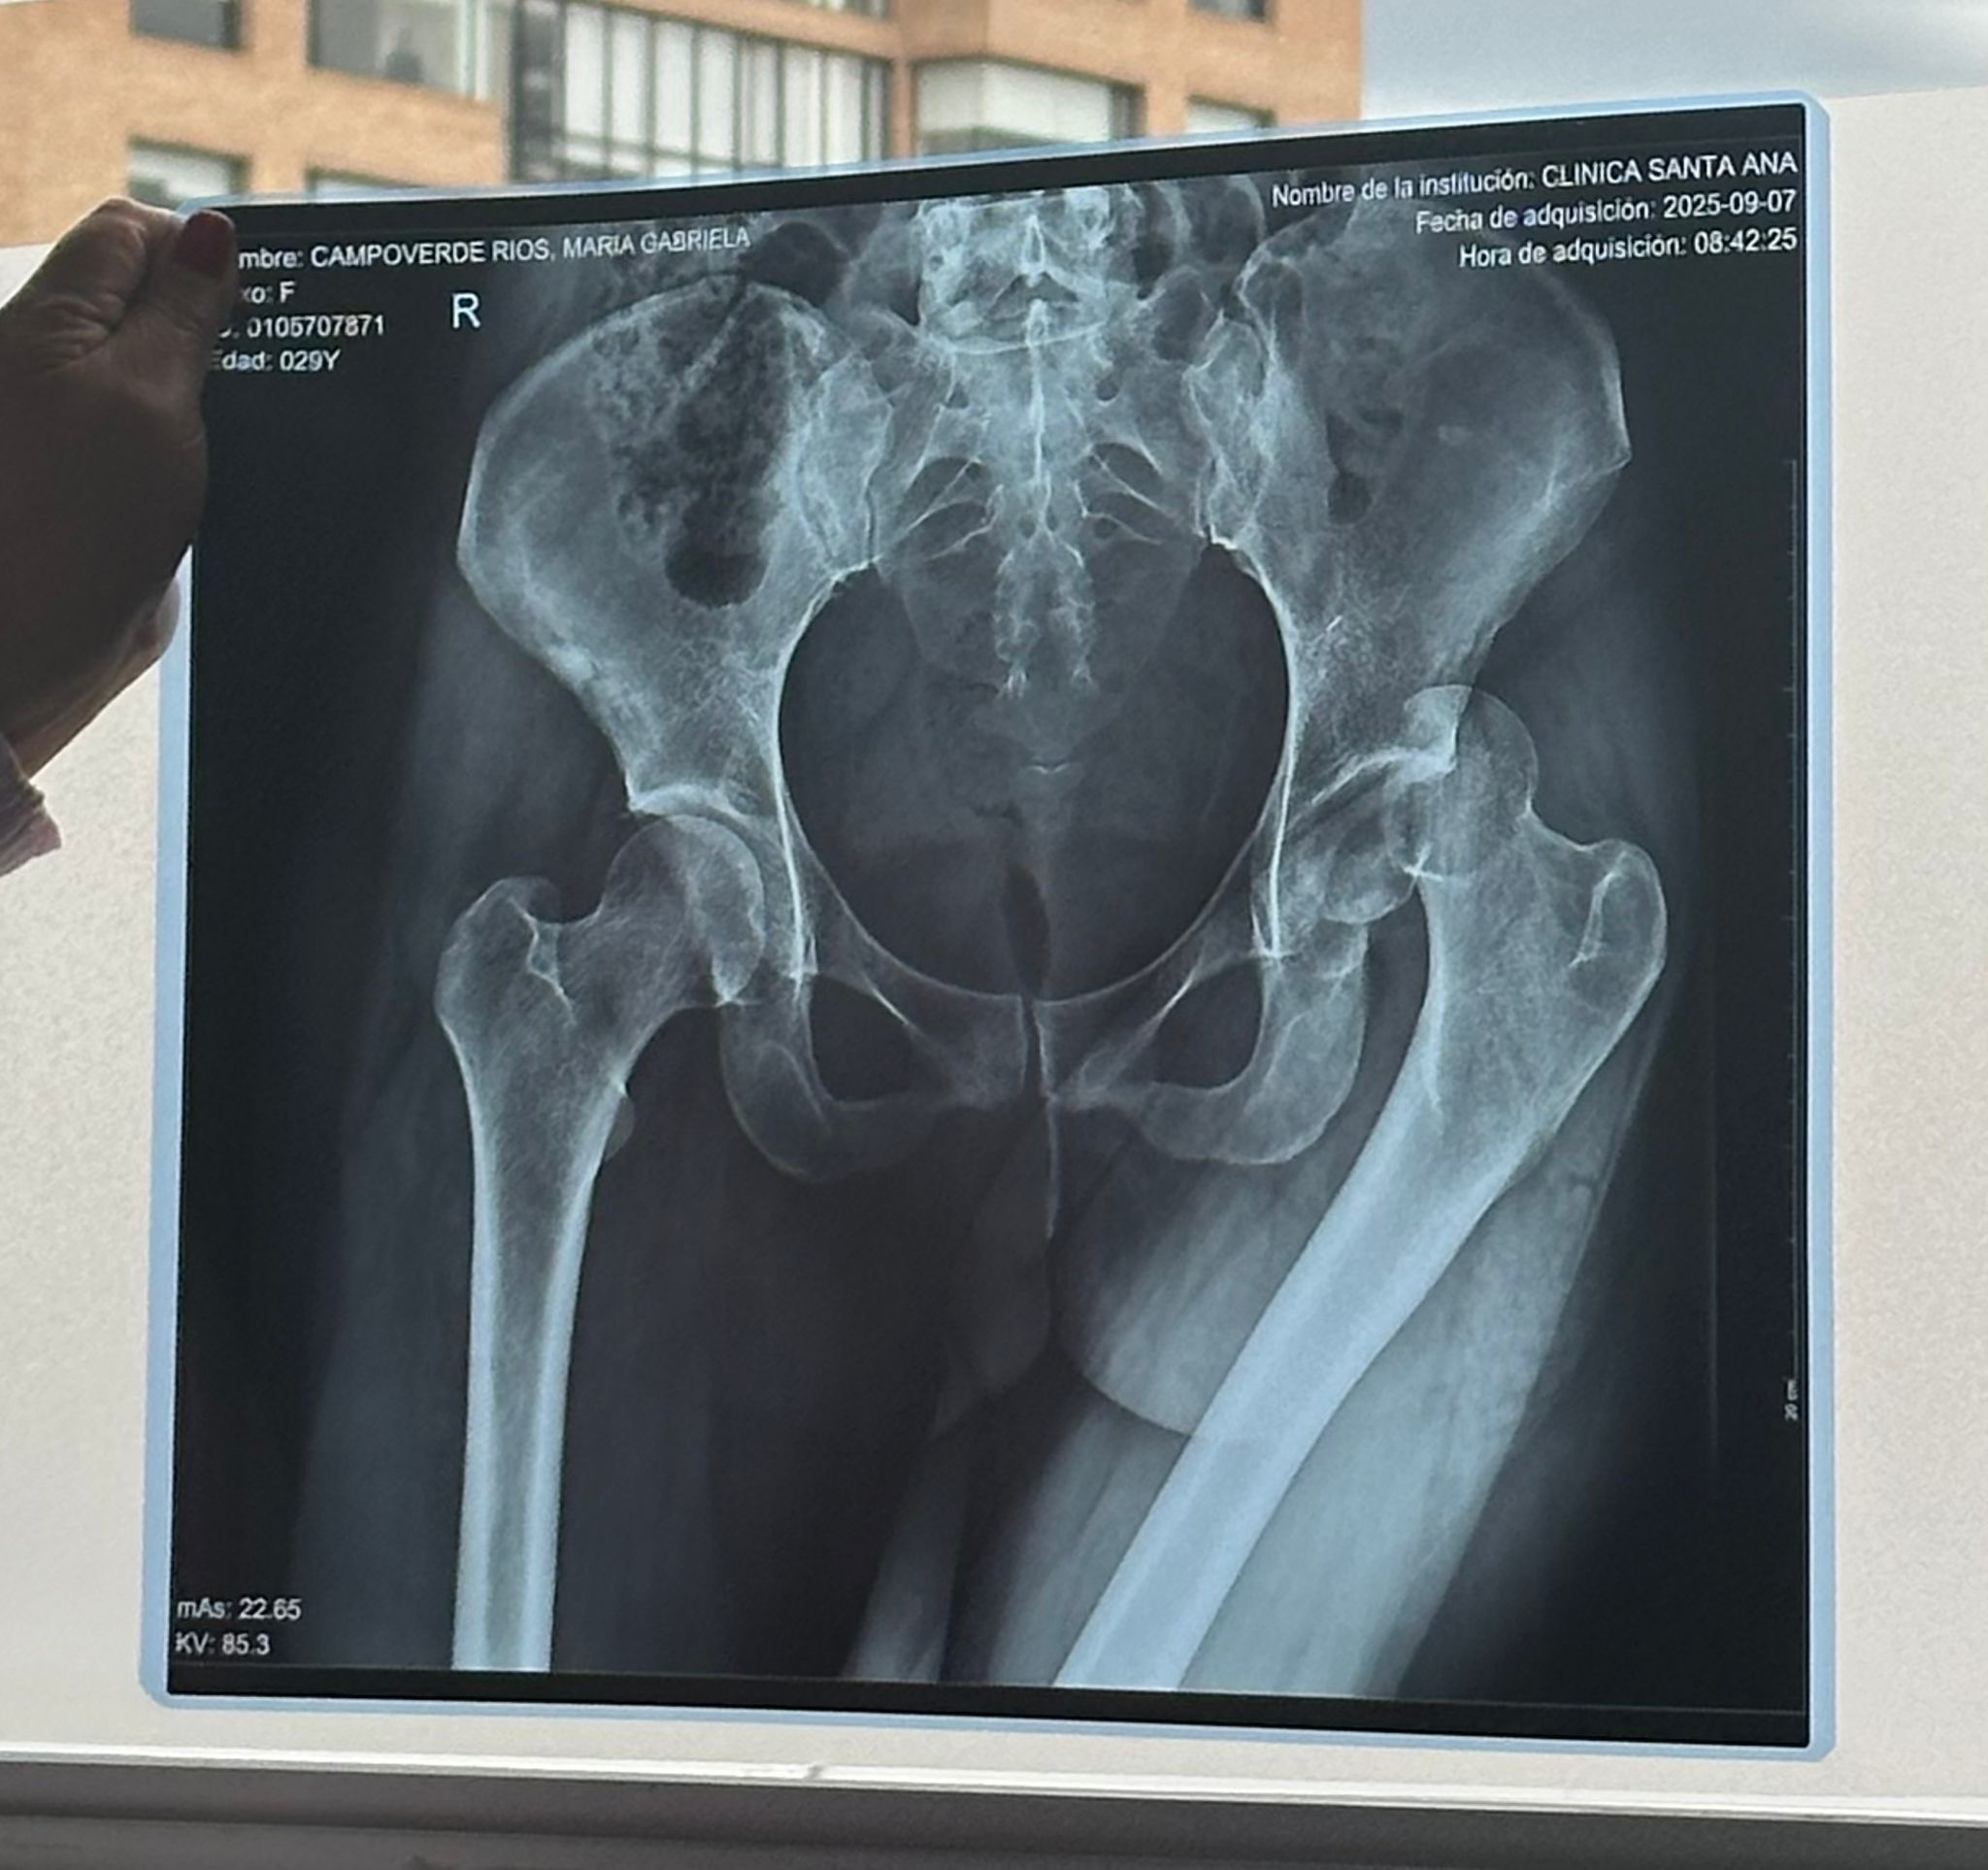

En la Clínica Santa Ana, Gabriela fue sometida a dos cirugías de emergencia:

• Reducción abierta y fijación interna con tornillos Herbert en la cabeza del fémur izquierdo.

• Septoplastia y reducción de fractura de huesos propios de la nariz y desviación del tabique.